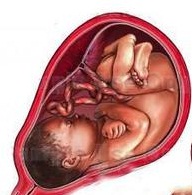

胎儿子宫位置示意图

孕2个月 孕3个月 孕4个月 孕5个月 孕6个月 孕7个月...